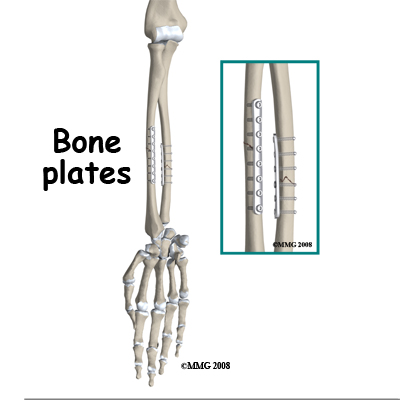

In the majority of cases, the surgeon will recommend surgery to ensure that the fracture is reduced accurately and fixed with internal fixation. Fixation with plates and screws is a common method although some surgeons recommend the less invasive method of placing a rod into the hollow medullary cavity of the bone, called intramedullary fixation.

Because fixation allows early recovery of movement of the forearm and hand, the long-term risk of stiffness and loss of function are reduced. After surgery (internal fixation) a cast is not usually necessary although weight should not be put through the limb until the bone is healed. A sling for protection and pain relief is the usual practice but unloaded hand, wrist, and elbow movements can be started right away.

Removal of the implants is controversial. The hardware is often uncomfortable and in those cases the patient and surgeon usually agree to removal. However, about 1/10th of these cases have a re-fracture within six weeks of the removal operation. This risk deters some surgeons from removal of the hardware where there are no symptoms. Others believe that the life time risk of a problem from a retained plate is great enough to warrant removal of plates as a precaution.

Painful Hardware

The plates and screws used to immobilize the fracture fragments may be tender. Sometimes they can be felt under the muscle layers and are sore when you rest your arm on a table. Very commonly there is a persistent ache that may be increased by weather changes. The reasons for this symptom are not known but removal of the hardware eliminates the problem.

Surgery to remove the plates and screws is often done once the bones have healed. However, there is a well recognized risk of refracture in the first few weeks after plate removal and patients are advised to be protective of their arm during this period.